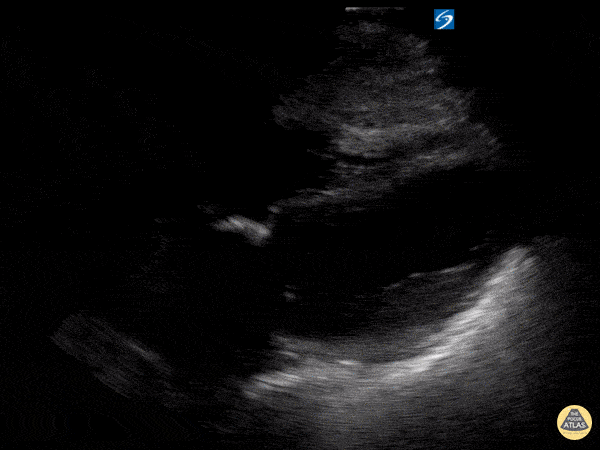

Left Ventricular Dysfunction - Apical Ballooning 2

A 50 years old, complaining of dyspnoea and chest pain. She had no prior history of cardiopulmonary disease. Initial ultrasound of the lung fields demonstrated plenty of B-lines bilaterally. An subxiphoid cardiac view demonstrates hypokinesis & aneurysmal dilation of the apex consistent with Takotsubo's cardiomyopathy. The patient's heart failure was managed supportively and a catheterization was performed during hospitalization that showed normal coronary artery stenosis. She had a full recovery Ilan Ben-Shabat 5th year medical student Aspiring emergency physician